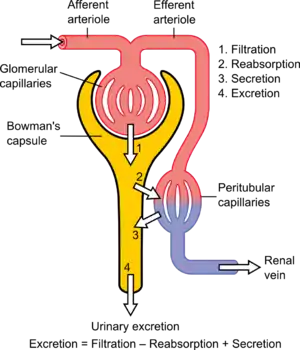

The four mechanisms used to create and process the filtrate (the result of which is to convert blood to urine) are filtration, reabsorption, secretion and excretion. Filtration or ultrafiltration occurs in the glomerulus and is largely passive: it is dependent on the intracapillary blood pressure. About one-fifth of the plasma is filtered as the blood passes through the glomerular capillaries; four-fifths continues into the peritubular capillaries. Normally the only components of the blood that are not filtered into Bowman's capsule are blood proteins, red blood cells, white blood cells and platelets. Over 150 liters of fluid enter the glomeruli of an adult every day: 99% of the water in that filtrate is reabsorbed. Reabsorption occurs in the renal tubules and is either passive, due to diffusion, or active, due to pumping against a concentration gradient. Secretion also occurs in the tubules and collecting duct and is active. Substances reabsorbed include: water, sodium chloride, glucose, amino acids, lactate, magnesium, calcium phosphate, uric acid, and bicarbonate. Substances secreted include urea, creatinine, potassium, hydrogen, and uric acid. Some of the hormones which signal the tubules to alter the reabsorption or secretion rate, and thereby maintain homeostasis, include (along with the substance affected) antidiuretic hormone (water), aldosterone (sodium, potassium), parathyroid hormone (calcium, phosphate), atrial natriuretic peptide (sodium) and brain natriuretic peptide (sodium). A countercurrent system in the renal medulla provides the mechanism for generating a hypertonic interstitium, which allows the recovery of solute-free water from within the nephron and returning it to the venous vasculature when appropriate.

Functions

The nephron uses four mechanisms to convert blood into urine: filtration, reabsorption, secretion, and excretion.[4]: 395–396 These apply to numerous substances. The structure and function of the epithelial cells lining the lumen change during the course of the nephron, and have segments named by their location and which reflects their different functions.

Proximal tubule

The proximal tubule as a part of the nephron can be divided into an initial convoluted portion and a following straight (descending) portion.[11] Fluid in the filtrate entering the proximal convoluted tubule is reabsorbed into the peritubular capillaries, including 80% of glucose, more than half of the filtered salt, water and all filtered organic solutes (primarily glucose and amino acids).[4]: 400–401